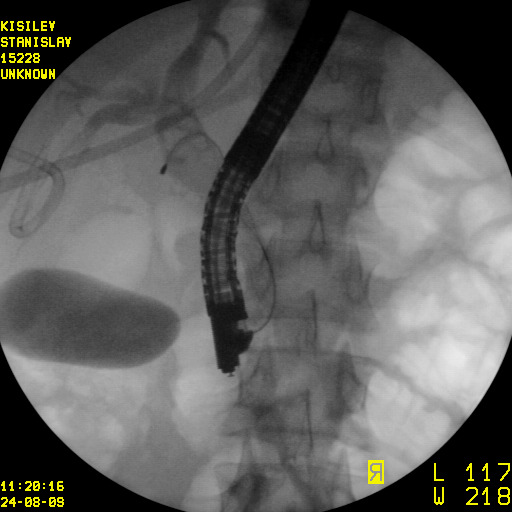

Минимально инвазивное лечение при эхинококковых кистах печени, осложнившихся прорывом в желчные протоки

Представлены клинические наблюдения редкого осложнения эхинококкоза печени – прорыва эхинококковой кисты в желчные протоки. Осложнение стало причиной обструкции желчных протоков, механической желтухи и холангита. Освещены этапы диагностики, роль УЗИ в выявлении осложнений эхинококкоза печени, рассмотрены способы минимально инвазивного лечения с применением эндоскопических и чрескожных технологий под контролем лучевых методов.